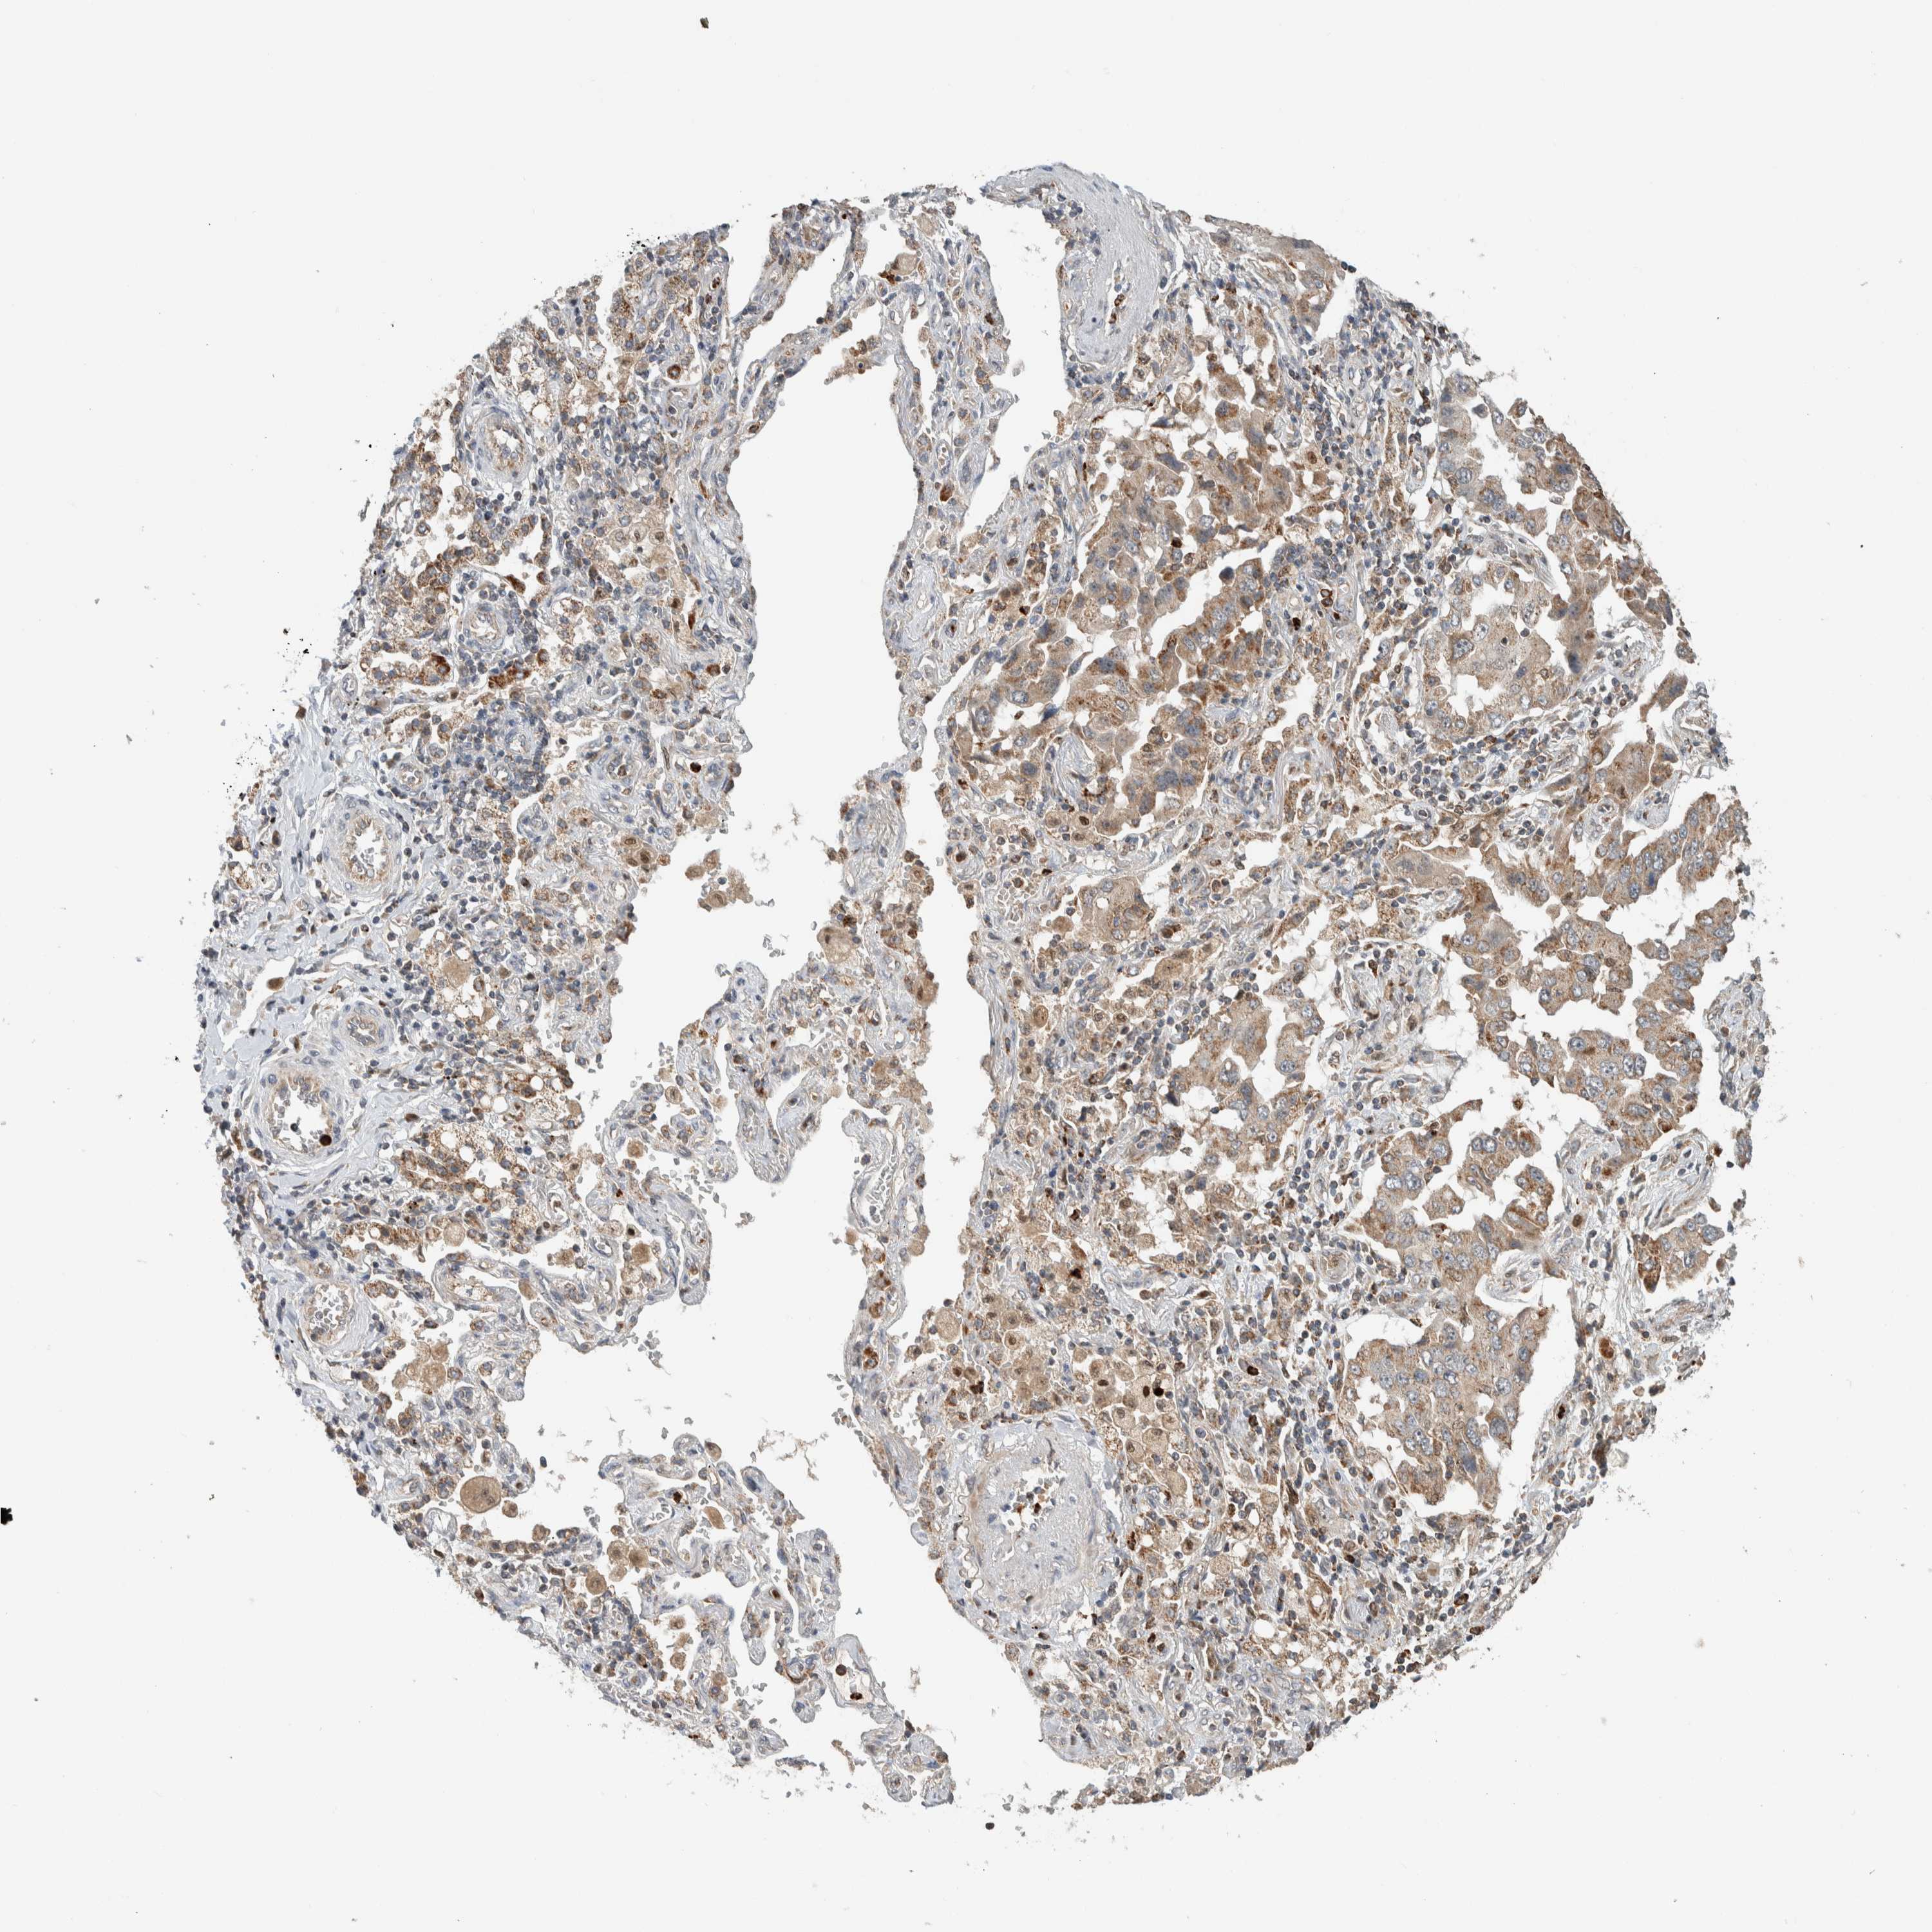

CANCER LUNG CANCER Show tissue menu

LUAD TCGA LUAD VALIDATION LUSC TCGA LUSC VALIDATION PROTEIN LUAD CPTAC PROTEIN LUSC CPTAC PROTEIN EXPRESSION